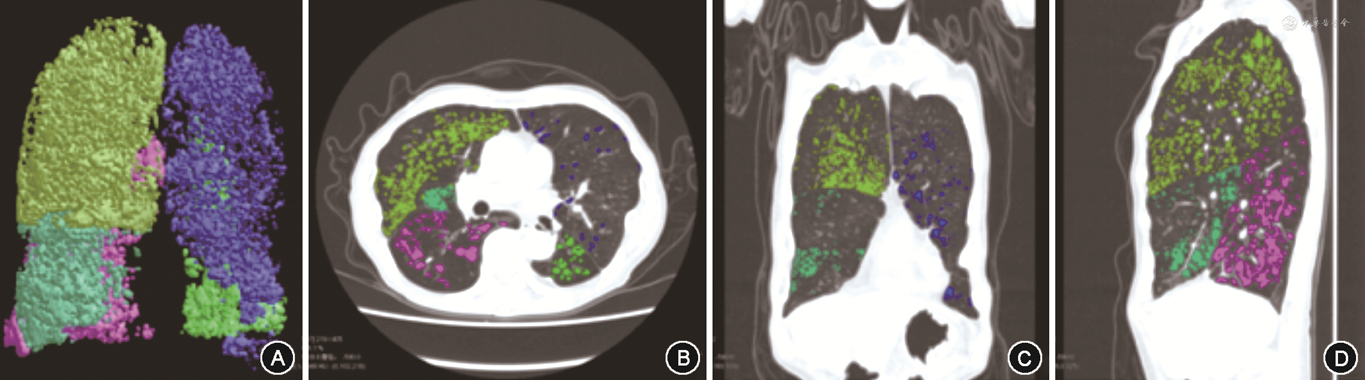

2.肺气肿参数:使用陕西渭南神州德信医学成像技术有限公司自主研发的FACT医学影像信息系统(陕械注准20232210007)处理HRCT原始DICOM数据并自动测量[15]。使用-950 HU作为阈值,低于该阈值区域标记为肺气肿区域。通过FACT智能几何技术计算出肺气肿区域占全肺容积的百分比,得出肺气肿指标像素指数-950(pixel index-950,PI-950)(图1)。

注:CT值<-950 Hu标记为肺气肿区域,各肺叶使用不同颜色,不同角度呈现;通过FACT智能几何技术计算出肺气肿区域占全肺容积的百分比,即得出PI-950